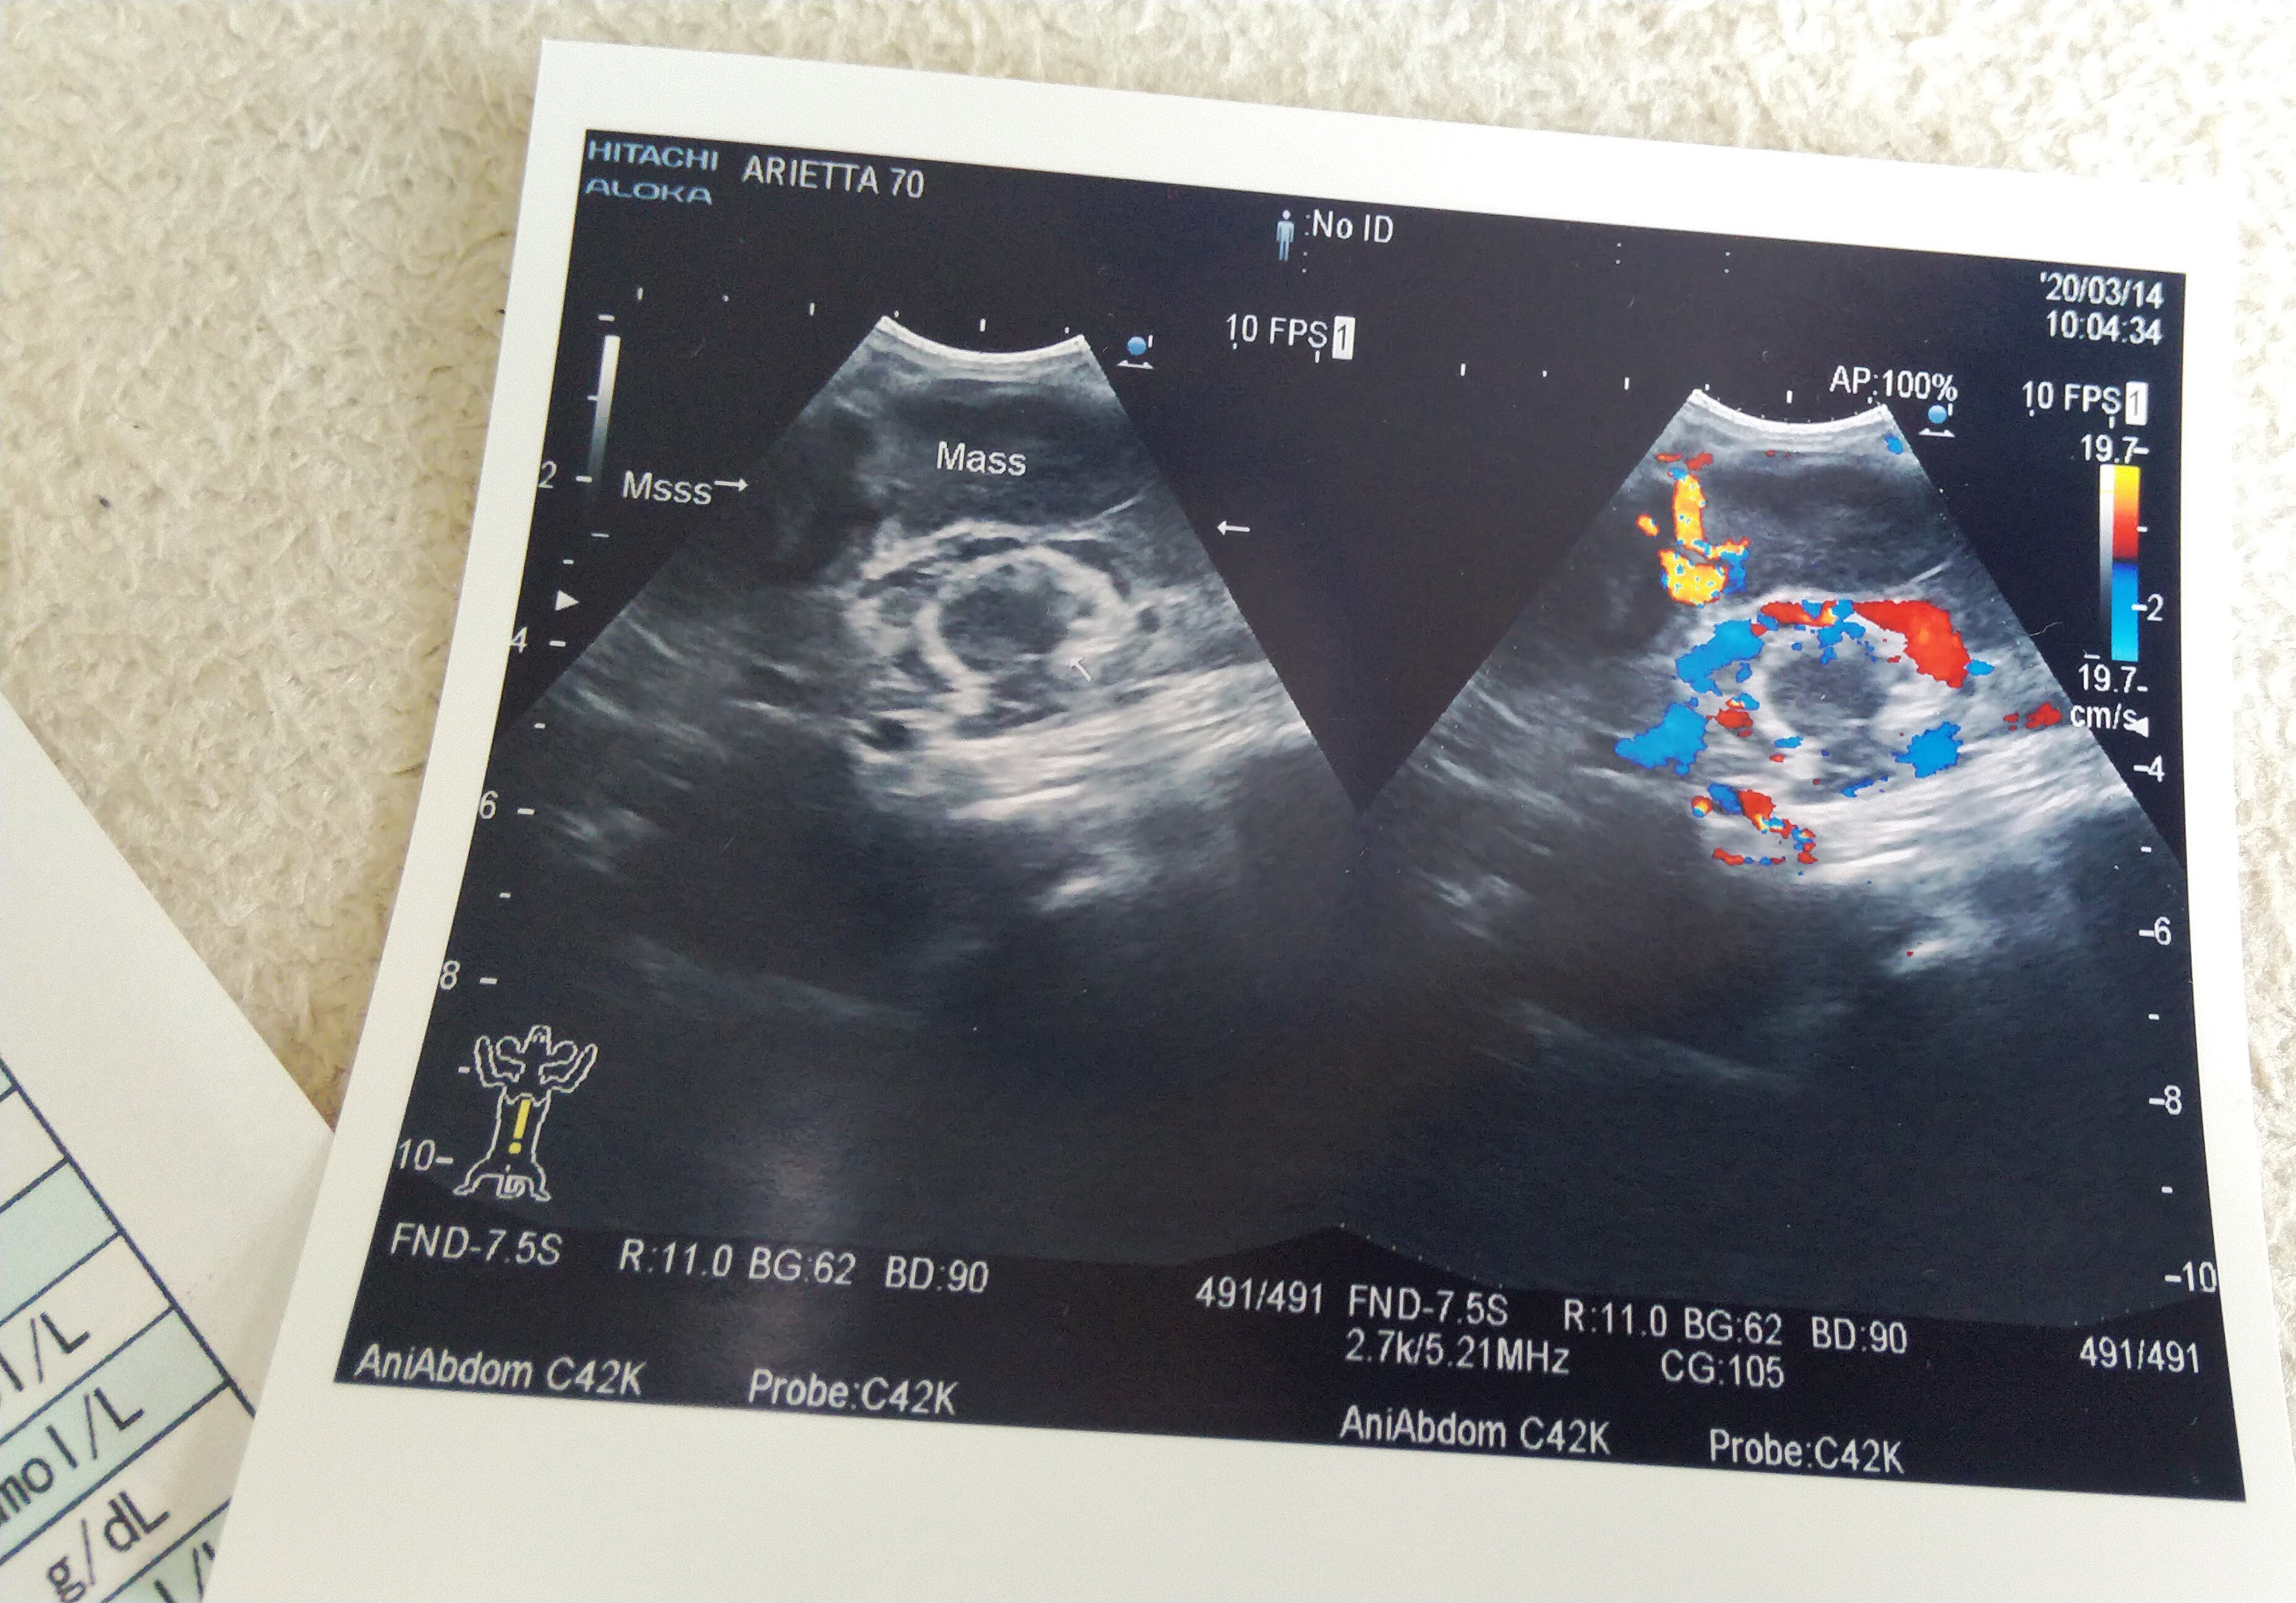

血液、尿検査、心電図、エコーすべてとって出たのは「貧血」「膵炎」「飢餓による腹水」「腸のむくみ」とオンパレード…

しかも、CTを撮ったところ「リンパ腫」まで判明。

エコーでわかった大きな腫瘍。A病院が早く検査してくれれば、こんな大きさになる前にわかったはずなのに…